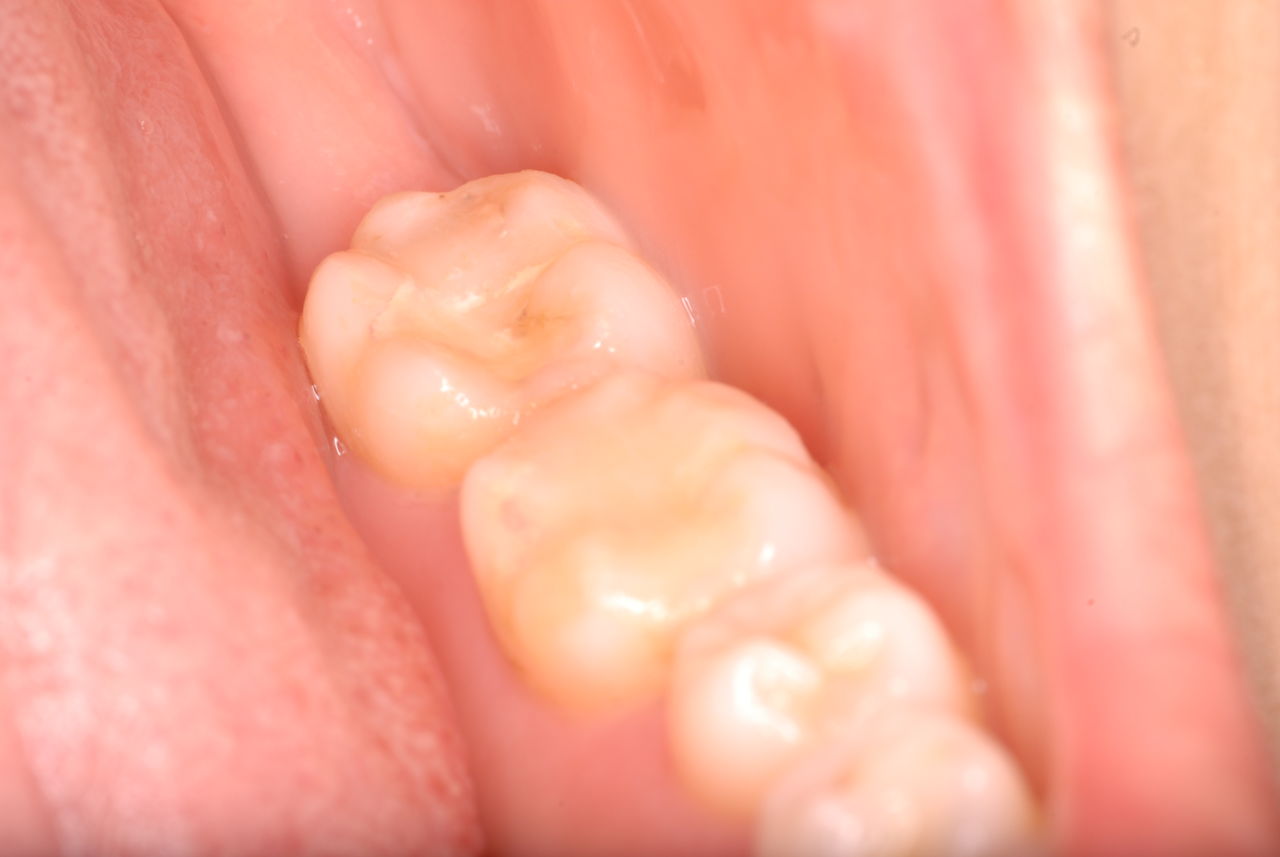

今日のすべての患者さんは、一人を除いて新患を含めてすべて歯周病の方でした。

歯周病は殆どの方に存在し、気づかないうちに進行していきます。

そして場所や痛みなどの症状がはっきりしないのです。冷たい水がしみることもあります。

なかなかブラシの使い方ができていないようで、歯磨きと歯周病でのブラシの使い方は別なのですが、習ったことも検査もされずに金属を被せたりしているようで、これからも歯医者さんで抜かれたり、その後にインプラントのような高価な“クギ”を打ち込まれる方が増えるかと思うと残念です。

まず検査をして、ブラシの使い方を習得して歯医者さんで削ったり抜かれたりしないように予防に注意する方々が増えないかと思う日々です。

被せても、詰めても病気は治らないのですから。又病気の元になり易い不適合な差し歯や金属、インプラントがあればそこからバイキンが侵入して体に悪さもしやすいのではないかと心配しています。